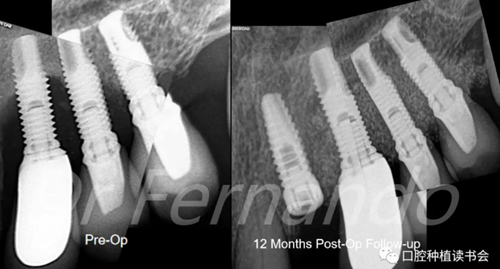

圖23 術(shù)后15天術(shù)區(qū)恢復(fù)健康

經(jīng)過12個(gè)月的隨訪,患者取得了良好的臨床效果,24位點(diǎn)種植體最終的曲面斷層片和根尖片,臨床顯示在種植體相應(yīng)部位的腭側(cè)病變?nèi)肯?,骨小梁恢?fù)良好。病人沒有任何不適癥狀(圖 24)。

圖24 術(shù)后12個(gè)月骨再生效果良好